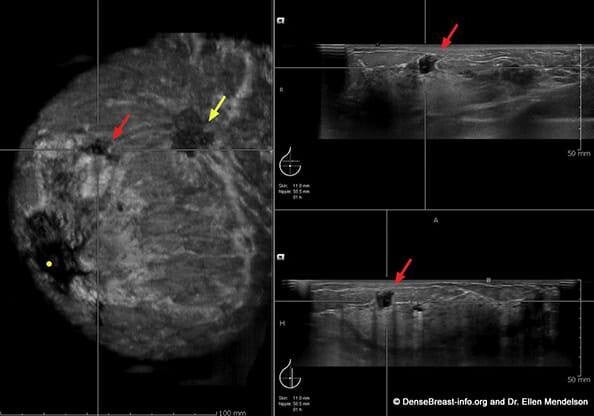

If you experience any symptoms, your doctor may recommend several diagnostic tests. These may include a clinical breast exam, mammogram, ultrasound, MRI, and/or biopsy. A biopsy, where a small tissue sample is taken for examination, is the only way to confirm a diagnosis of breast cancer. Understanding the purpose of each test can help alleviate anxiety and ensure you're an active participant in your healthcare.